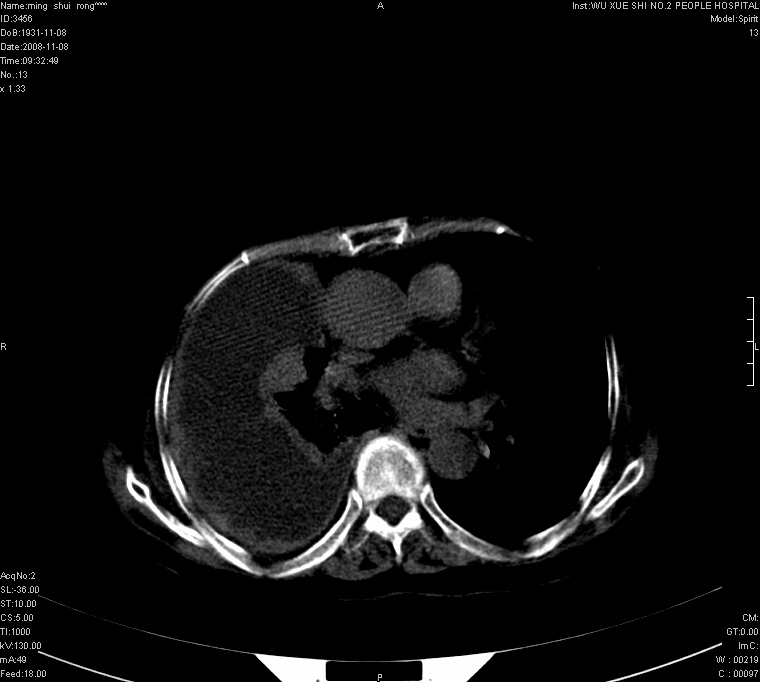

75.女.胸痛

75.女.胸痛 。右侧胸廓稍塌陷,右侧胸膜广泛增厚,并见多发结节及肿块影,右侧大量胸腔积液,纵隔固定无移位;首先考虑恶性病变,胸膜间皮瘤可能性大。

75.女.胸痛 。右侧胸廓稍塌陷,右侧胸膜广泛不规整增厚,并见部分肺组织实变,右侧大量包裹性胸腔积液,纵隔固定无移位;1.考虑结核性。  2,考虑胸膜间皮瘤可能性大。(建议胸水检查)

右侧胸腔可见弧形低密影,右侧胸膜广泛不规则增厚,右肺不张,纵隔右移。考虑:右侧恶性胸膜间皮瘤可能大,请结合临床。

75.女.胸痛 。右侧胸廓稍塌陷,右侧胸膜广泛增厚,并见多发结节及肿块影,右侧大量胸腔积液,纵隔固定无移位;首先考虑恶性病变,胸膜间皮瘤可能性大或肺癌胸膜转移。

右侧胸膜广泛增厚,并见多发结节及肿块影。右侧大量胸腔积液。考虑1.恶性胸膜间质瘤?2.胸膜转移瘤?建议胸水检查。